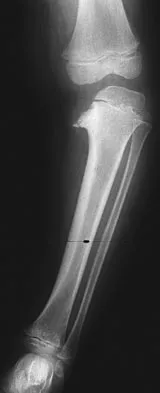

Examination of an obese 3-year-old girl reveals 30 degrees of unilateral genu varum. A radiograph of the involved leg with the patella forward is shown in Figure 10. Management should consist of

The clinical scenario describes infantile tibia vara (Blount's disease). The radiograph shows severe deformity with the characteristic Langenskiold stage 3 changes of the medial proximal tibial metaphysis that distinguish it from physiologic bowing. The preferred treatment is proximal tibiofibular osteotomy with acute correction into slight valgus to unload the damaged area of the physis. This method provides the best results in patients younger than age 4 years. Continued observation would result in progressive deformity. Bracing is most effective in younger children with less severe deformity. Lateral proximal tibial hemiepiphysiodesis relies on growth of the injured medial physis for correction and would result in severe tibial shortening in this young child. Complete epiphysiodesis also produces severe shortening and requires multiple lengthening procedures. Johnston CE II: Infantile tibia vara. Clin Orthop 1990;255:13-23.